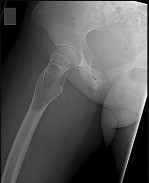

This patient has a dedifferentiated liposarcoma within a preexisting atypical lipomatous tumor. The imaging demonstrates a large fatty mass with increased internal septations proximally (the atypical lipomatous tumor) and a solid enhancing mass distally (the dedifferentiated portion). A biopsy reveals a high-grade liposarcoma. The other diagnostic responses do not reflect sarcomatous transformation of the lesion.

Surgical treatment of a high-grade sarcoma involves wide surgical resection. Radiation decreases local recurrence but does not clearly influence overall survival. The role of chemotherapy in high-grade soft-tissue sarcomas remains investigational; there is a modest (8%-15%) associated improvement in overall survival.

Intramuscular lipomas and atypical lipomatous tumors are treated with marginal resection alone. Radiation therapy for soft-tissue sarcomas may be given before or after surgery. When administered before surgery, patients have a higher wound complication rate but better long-term function attributable to lower rates of lymphedema, fibrosis, and contractures.